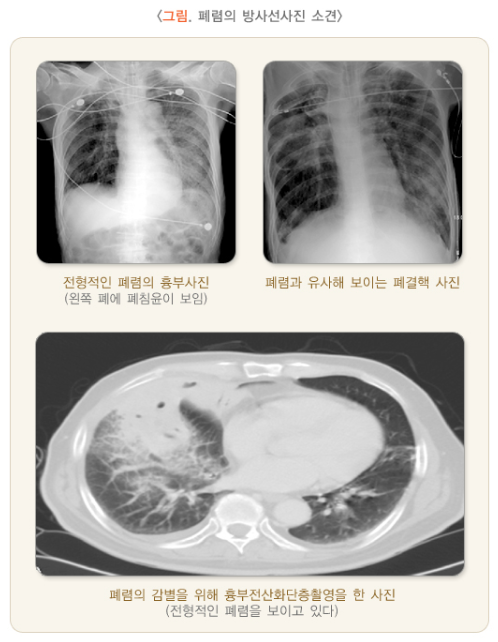

급성 폐렴은 급격히 진행되는 호흡기 질환으로, 치료가 지연되면 사망에 이를 수 있는 위험한 질병입니다.

급성폐렴은 빠르게 진행될 수 있으며, 심할 경우 사망에 이를 수 있습니다. 특히 면역력이 약한 고령층과 기저질환자에게 치명적입니다.